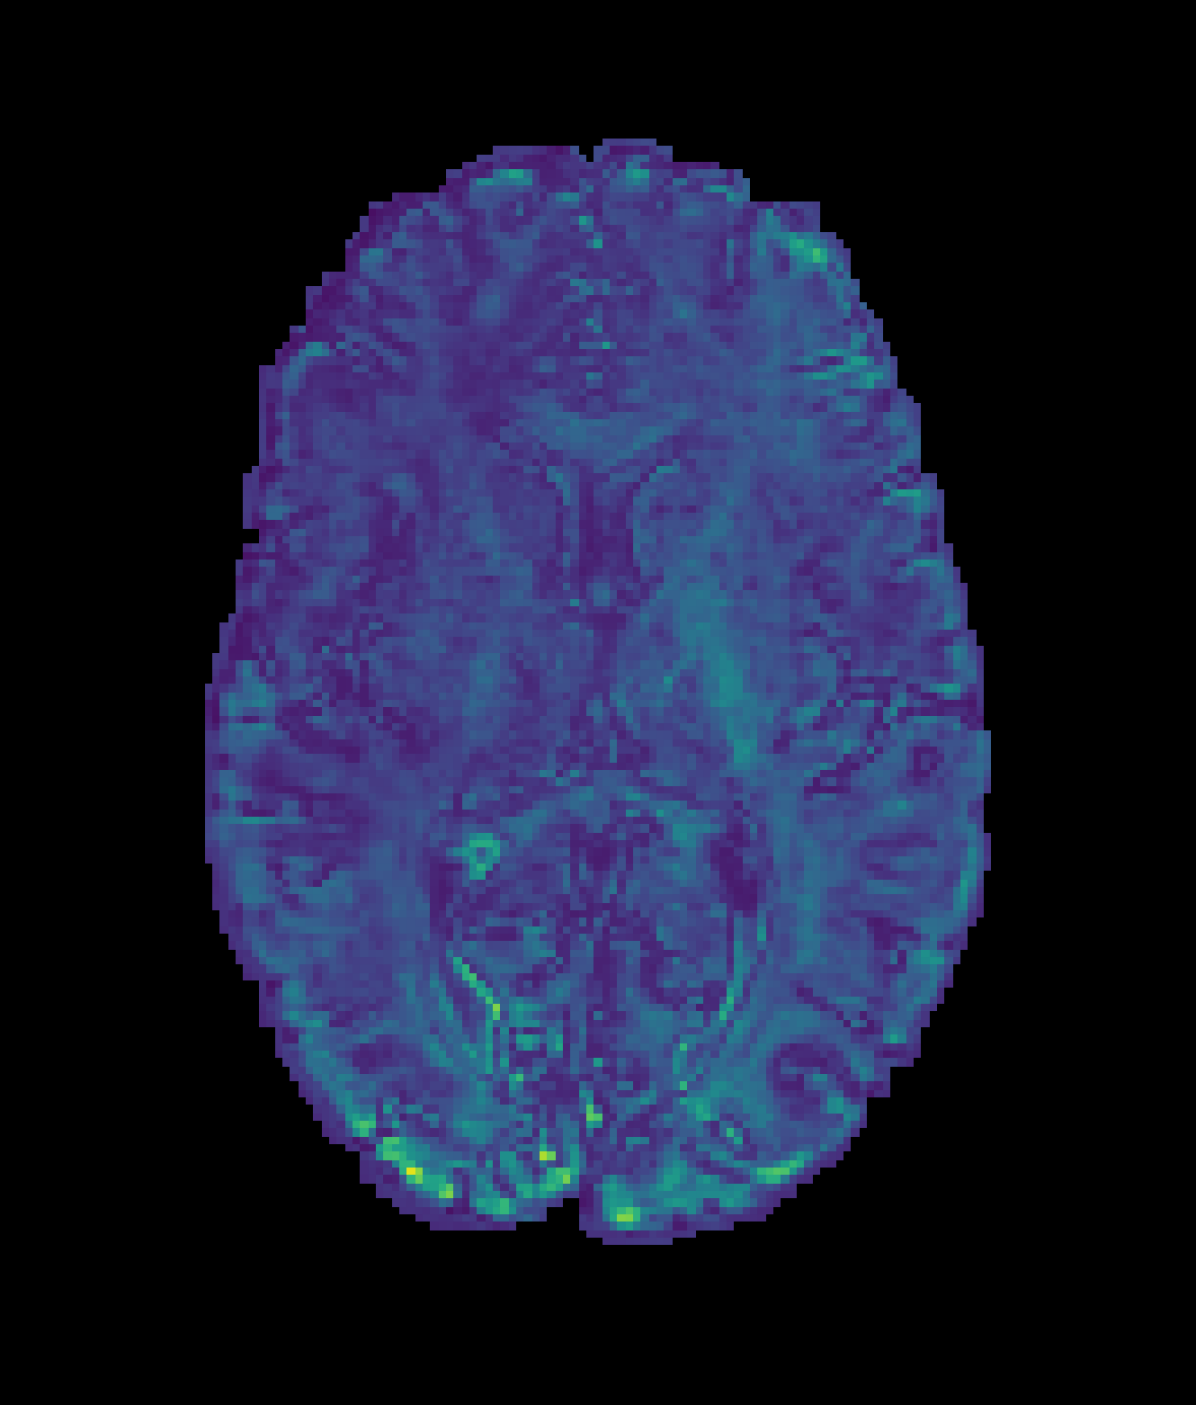

In this experiment, the PCCNN models perform competitively, yielding the lowest error in fisosubscript𝑓isof_{\mathrm{iso}} and fintrasubscript𝑓intraf_{\mathrm{intra}} across all three sub-sampling rates. The relative error in OD across different models mirrors that of the FOD ACC found in Table 4, suggesting that the trained models are able to infer data that generalise across different downstream analyses. The worst performing model across all sub-sampling schemes was the SR-q-DL model, as is demonstrated qualitatively by Figure 4. Whilst this model could benefit from the more constrained task of inferring NODDI data directly, the lack of geometric prior information, such as b-vector coordinates, suggests that these additions within the PCCNN models were important to its relatively high performance in this task.

Refer to caption

(a) High Resolution

(b) SR-q-DL

(c) RCNN

Refer to captionRefer to caption

(d) PCCNN-Bv

Figure 4: Axial slice of orientation dispersion index (OD) within one subject across different models. Models use single-shell data (b=1000s/mm2𝑏1000ssuperscriptmm2b=1000\mathrm{s/mm^{2}}) with angular dimension size qin=10subscript𝑞in10q_{\mathrm{in}}=10 as input, and produce 808080 b=1000s/mm2𝑏1000ssuperscriptmm2b=1000\mathrm{s/mm^{2}}, 909090 b=2000s/mm2𝑏2000ssuperscriptmm2b=2000\mathrm{s/mm^{2}}, and 909090 b=3000s/mm2𝑏3000ssuperscriptmm2b=3000\mathrm{s/mm^{2}} inferred volumes.